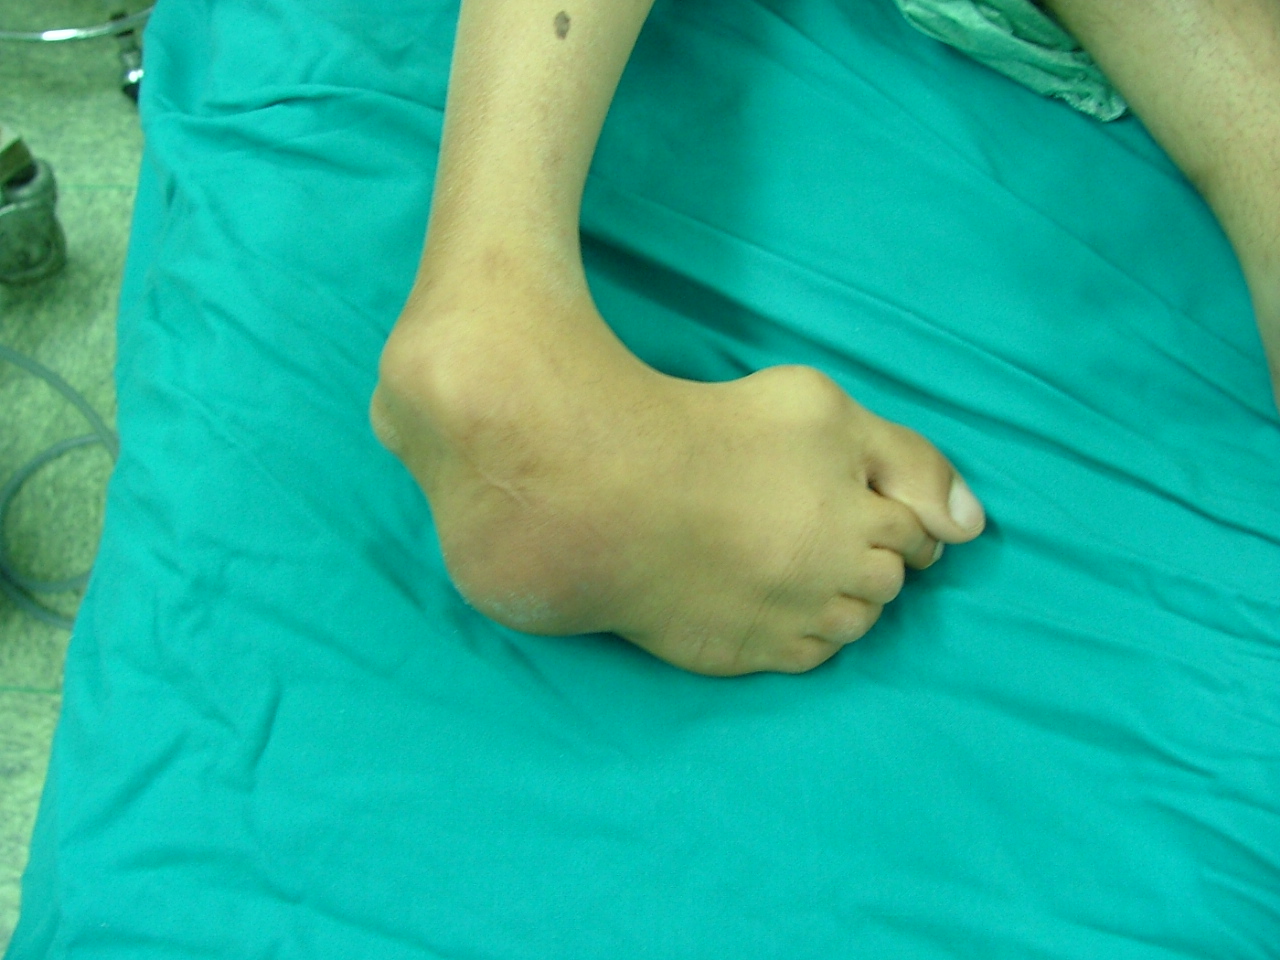

این عمل در مرکز جراحی ولنجک و زیر نظر دکتر حقانی فوق تخصص دست صورت گرفته

تاریخ عمل  پنج شنبه 20 شهریور 1393

شست کوتاه